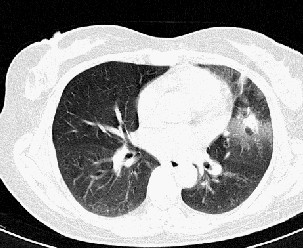

以下是引用汪涛同志在2007-5-15 21:54:00的发言:[br]左肺舌叶病变,周围渗出明显,病灶面积肺窗和纵隔窗有较大反差,同一叶前后病灶可见类似影像改变,后一病灶可见“直边征”考虑为渗出感染性病变,建议严格抗炎治疗后短期复查。